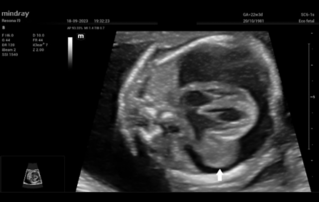

Ultrasound Journal 34 - Use of IOTA-ADNEX & O-RADS risk assessment models in MDT management of Adult Granulosa Cell Tumor

Comprehensive overview of granulosa theca cell tumors of the ovary, covering epidemiology, clinical presentation, diagnosis, treatment options, and prognosis for both adult and juvenile types.